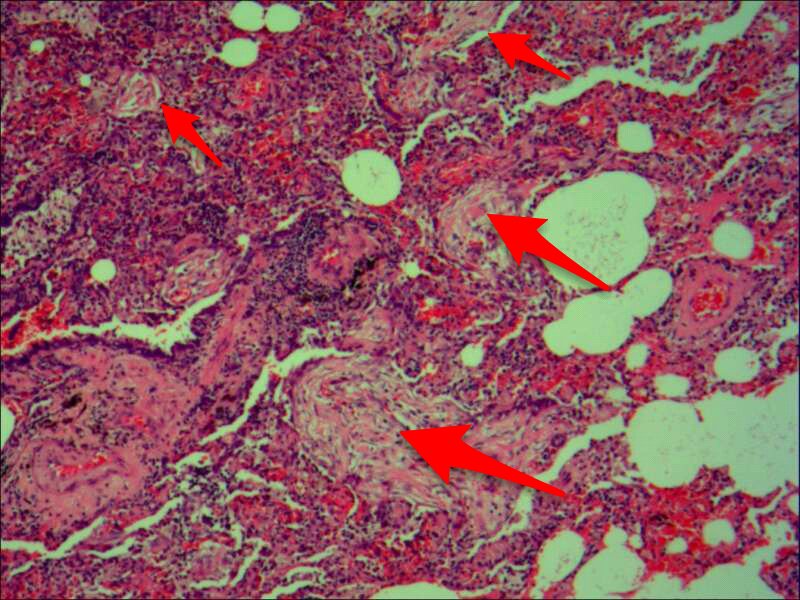

最后发一例化脓性炎症

中性粒细胞很多,此处组织结构破坏

左侧液化,脓肿壁较规则平滑

周围的炎症机化区

破坏力在这里逐渐减弱

逐渐从中性粒细胞转为淋巴细胞为主

周边区:

肺泡内有渗出,逐渐吸收 机化是不是纤维细胞增多看的?王:是的